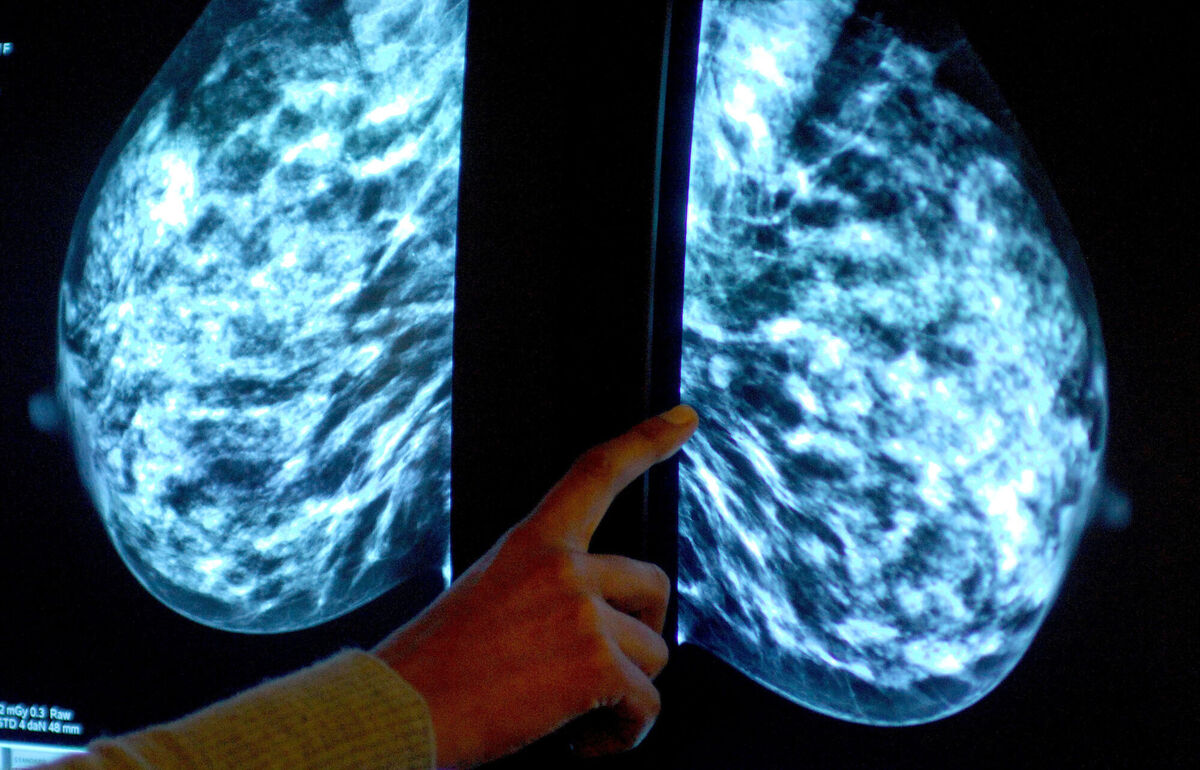

'It’s like smart chemo': New breast cancer treatment a 'game changer'

In early 2021, Avril Tierney received the news she had been dreading. At 43, she had been diagnosed with stage four metastatic breast cancer, which had spread to her lungs.

Having first been diagnosed with triple-negative breast cancer in 2019, a form of the disease which affects one in every eight breast cancer patients in Ireland, Tierney had already spent two years undergoing intensive chemotherapy and invasive surgery. Now she was confronted with her worst fears.

Every year, 3,700 women in Ireland are diagnosed with breast cancer with 690 deaths due to the disease.

But over the last decade, survival rates have advanced dramatically to the point where more than 80% of women with the disease will live for at least five years following diagnosis.

The major reason for this is the success of scientists in stratifying breast cancer into a whole array of subtypes, enabling oncologists to tailor the treatments that patients receive with increasing degrees of precision.